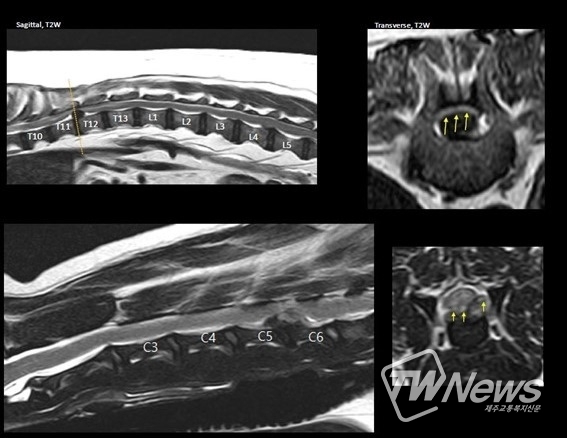

우선 치료를 위해서는 동물이 앓고 있는 추간판탈출증에 대해서 명확하게 분석할 필요가 있다. 정확히 어느 척추 사이 레벨인지, 어느 방향인지, 추간판 탈출 양의 정도는 얼마만큼인지, 이로 인한 척수의 손상은 어느 정도 인지를 확인하는 것이 도움이 된다. 이를 위해서는 X-Ray, MRI 등 최첨단 촬영을 통해 더욱 정확하게 진단을 받는 것이 도움이 된다.